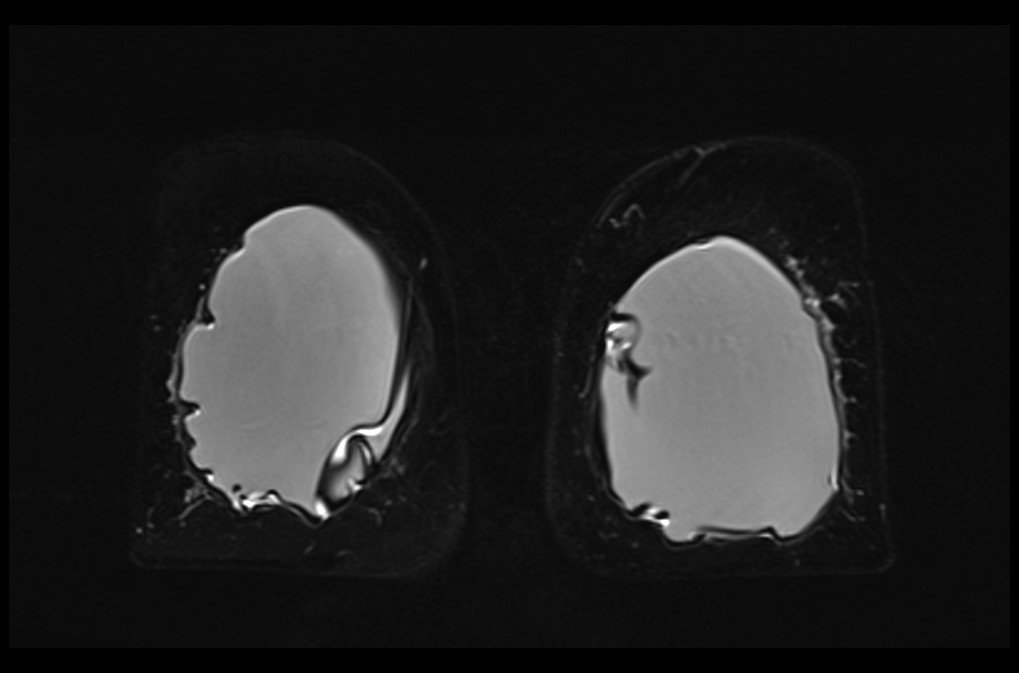

MRI breast implant stir coronal images 1 - MRI

MRI breast implant stir coronal images 2 - MRI

MRI breast implant stir coronal images 3 - MRI

MRI breast implant stir coronal images 4 - MRI

MRI breast implant stir coronal images 5 - MRI

MRI breast implant stir coronal images 6 - MRI